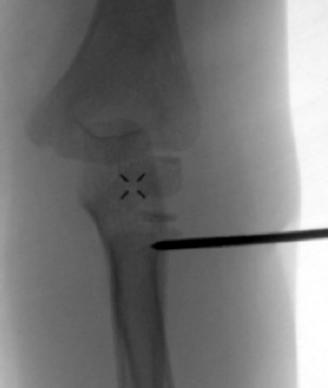

• Closed Reduction and Percutaneous Pinning

• K-wire joystick technique

• push technique

• blunt end of a large k-wire is pushed against the posterolateral aspect of the proximal fragment and pushed into place

• lever technique

• k-wire is placed into the fracture site and levered proximally

• if unstable after reduction a pin may be placed to maintain reduction